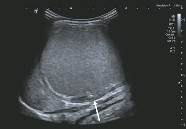

2岁 女孩,右腹部肿块

| 脊柱两侧病变活检 |

病理:神经母细胞瘤